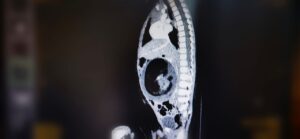

عملية جراحية نادرة في المستشفى السلطاني لاستئصال جنين من داخل جنين

أجرى قسم جراحة الأطفال بالمستشفى السلطاني عملية جراحية نادرة تتمثل في استئصال جنين من داخل جنين، وهي حالة تعد نادرة الحدوث عالميًا؛ لكونها تتم في ظروف استثنائية. .

يُذكر أن هذه الظاهرة الطبية تُعرف بـ

” Fetus in feto “

وتحدث بنسبة 1 من كل 500 ألف حالة ولادة حية على مستوى العالم.